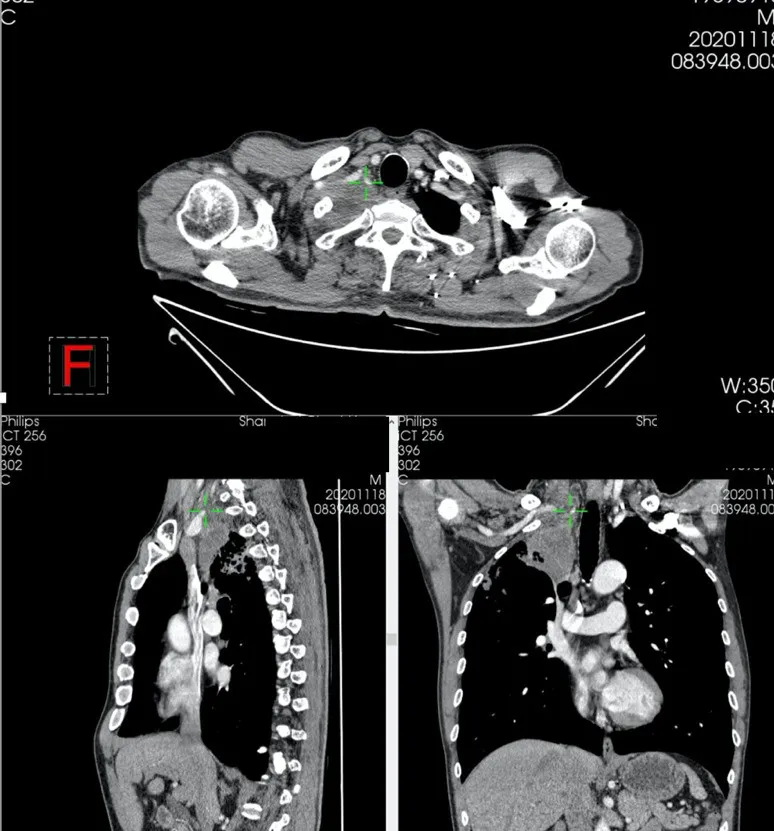

病變足足有8公分,從片子上看,鎖骨下血管,尤其是頭臂靜脈基本上看不到了,完全被腫瘤吃了,難怪病人胳膊很腫。第一肋、第二肋、鎖骨、第一椎體似乎也有侵犯。

非本例患者

我和進修老師們一起看了看片子,雖然腫瘤縮小了很多,中間還有個大空洞,但肺尖部的重要結構還是看不清楚,被腫瘤完全侵犯。

PET-CT提示仍有代謝活性。不切除,肯定會復發。